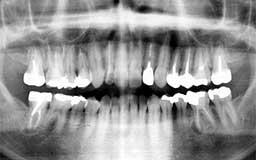

★ Pさん 52歳

年齢層をもう少し下げてみましょう。Pさんは来院時が52歳で、親知らずを除く喪失歯が

1本もなく健全そうにみえました。Oさん同様治療終了後の数年間にブランクがありました。

今から14年前の来院時にはメインテナンスを行うことの大切さがかなりはっきりわかってい

ましたので、それまでの経過を踏まえて少し強引にメインテナンスを勧めました。それ以降

はほとんど途切れることなくメインテナンスを継続されています。右の上顎第一大臼歯の1/3

だけ抜歯(ヘミセクション)していますので正確には現在残存歯数は27本と2/3ということ

になりますが、補綴(ほてつ)物も少なく10年後が楽しみな患者さんです。

| Pさん 初診時 52歳 男性 歯周疾患の進行傾向が随所に認められるが、年齢の割には比較的良好 |

Pさん 20年後 71歳 清掃状態は決して良好とはいえないが、20年間毎月メインテナンスを継続し良好な状態を保っている |